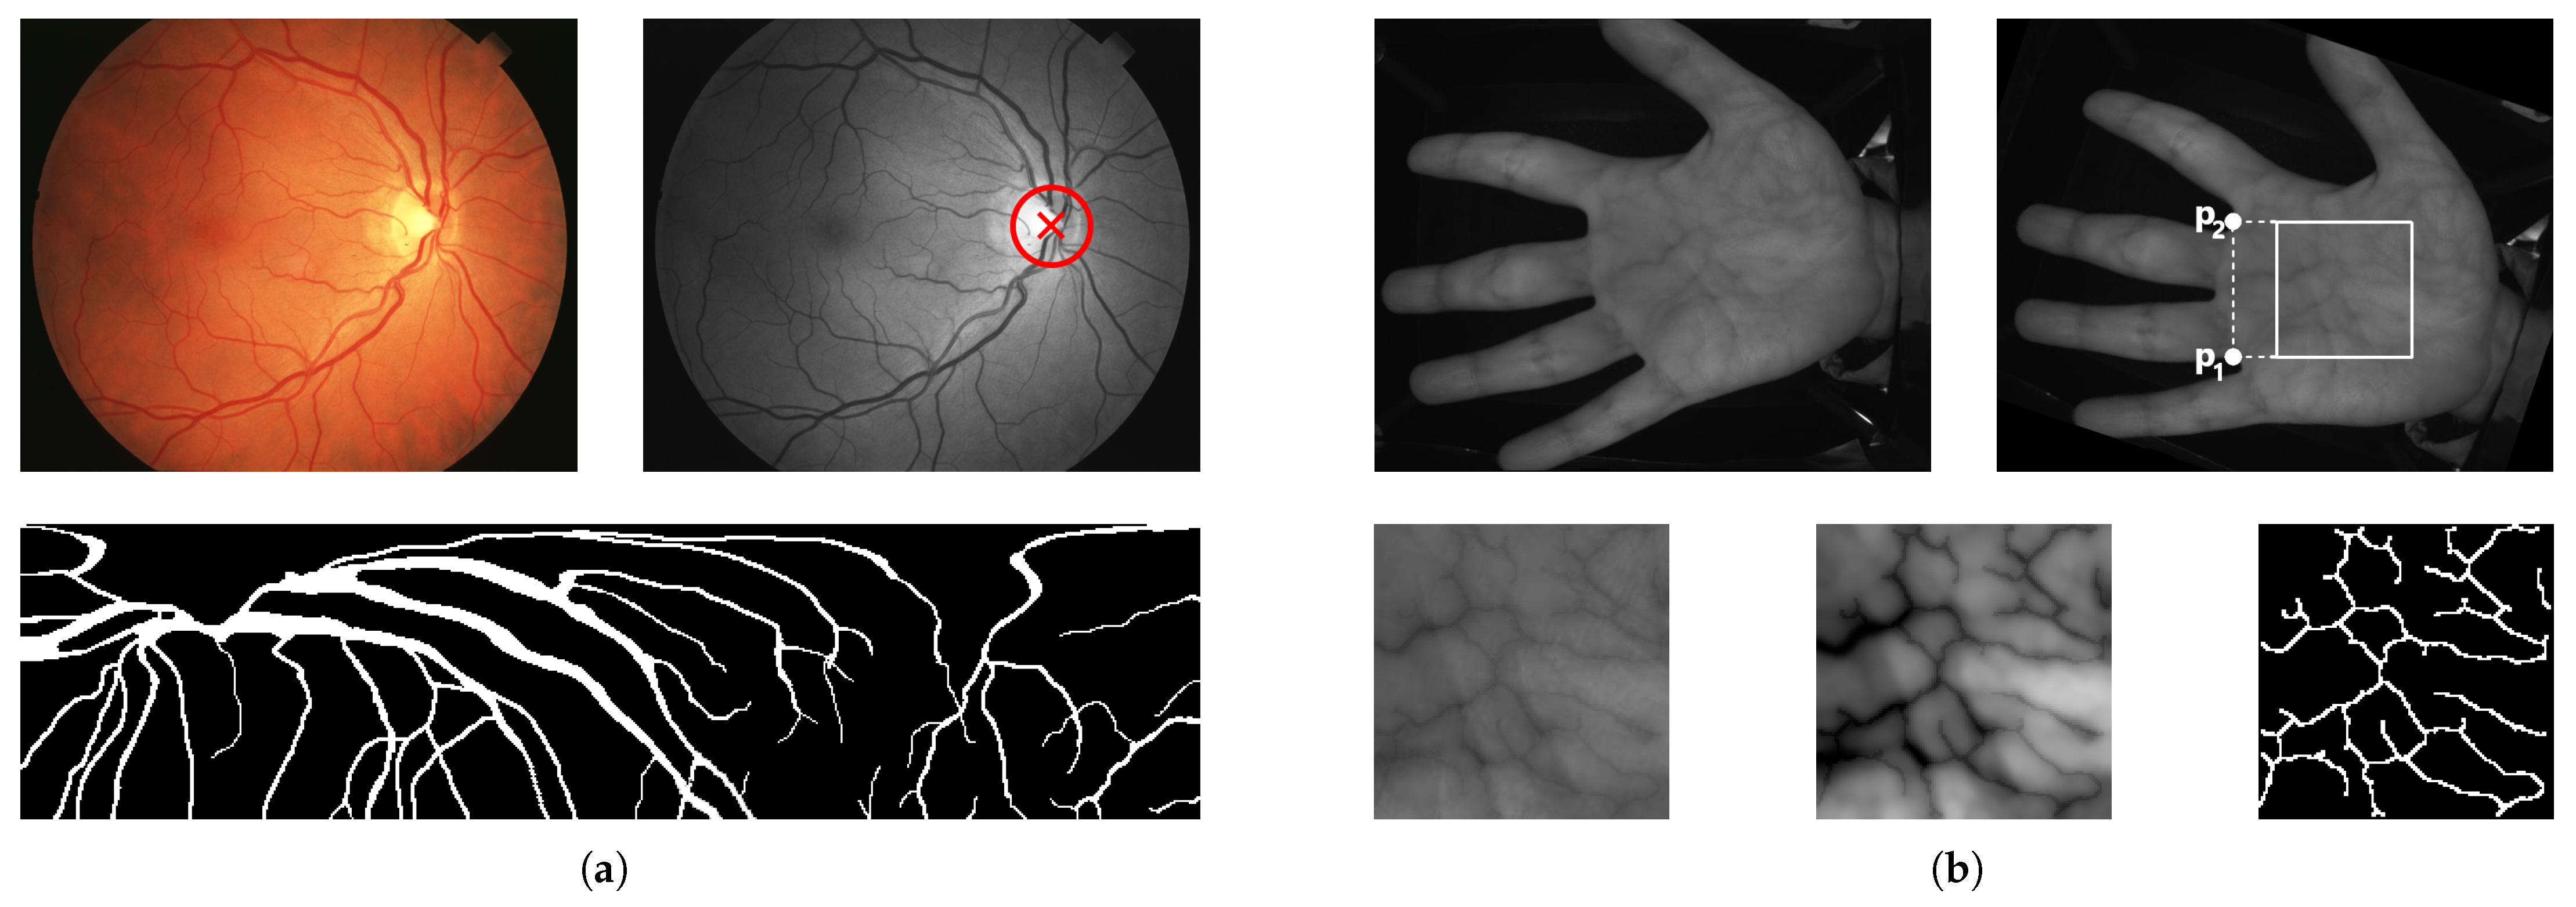

| RIDB | CASIA MSPD | |

|---|---|---|

| Modality | Retinal fundus | NIR palm vein |

| Number of subjects | 20 | 100 |

| Samples per subject | 5 | 12 |

| Total images | 100 | 7200 |

| Data format | JPEG, 24 bpp (colour) | JPEG, 8 bpp (grayscale) |

| Resolution (pixels) | pixels | pixels |

| Acquisition device | TOPCON TRC-50EX camera | Custom NIR imaging device |